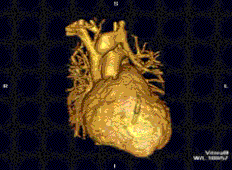

MR angiogram in congenital heart disease

Cardiac MRI is complementary to other imaging techniques, such as echocardiography, cardiac CT, and nuclear medicine. It can be used to assess the structure and the function of the heart.[30] Its applications include assessment of myocardial ischemia and viability, cardiomyopathies, myocarditis, iron overload, vascular diseases, and congenital heart disease.[31]